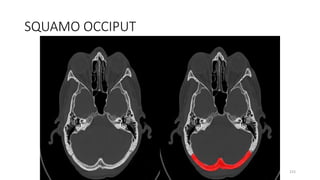

SQUOMOS OCCIPUT

188

203

SQUAMO OCCIPUT

215

SQUAMOUS OCCIPITO

225

SQUAMO- OCCIPITO

234